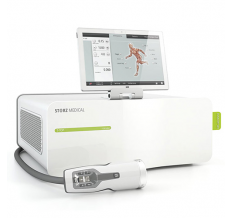

Высокие частоты ударных волн, максимальное введение ударных волн в ткани, оптимизированное давление применения и удобная технология сенсорного экрана. Теперь возможно: »Биомеханическая стимуляция« (BMS) с D-ACTOR® технологией!

Биомеханическая стимуляция (BMS) выполняемая при помощи технологии D-ACTOR® базируется на механическом применении вибрирующих импульсов на напряженные, сокращенные или перегруженные мышцы и сухожилия посредством физиологических частот ударов (18 – 21 Гц) и низких амплитуд вибраций передатчиков ударов D-ACTOR®. В результате, проприоцепция управляется, ткани очищаются и улучшается взаимодействие между центральной и периферической нервными системами.

Встроенная в аппарат функция вакуумной терапии расширяет спектр его применения в комплексном лечении. Различные диаметры банок дают возможность точно подобрать оптимальный размер для обрабатываемой зоны. Отверстие в куполе банке даёт возможность изменения вакуума на 47 %.

Аппарат имеет 30 встроенных программ лечения наиболее распространённых заболеваний:

Для каждого выбранного заболевания на дисплее показывается анатомическая зона лечения, изображения положений аппликатора и видеофильм по проведению процедуры.

Технические характеристики |

Значение |

| Тип ударной волны | радиальная |

| Принцип действия | пневматический |

| Частота ударов (Гц) | одиночные; 1-21 |

| Шаг регулировки частоты ударов (Гц) | 1 |

| Частота виброимпульсов (Гц) | 1-35 |

| Рабочее давление (бар) | 0,3-5 |

| Шаг регулировки рабочего давления (бар) | 0,1 |

| Максимальное давление в тканях (МПа) | 18,5 |

| Плотность потока энергии (мДж/мм2) | до 0,63 |

| Глубина терапевтического эффекта (мм) | 0-40; 50; 60 (в зависимости от сменной головки) |

| Дисплей аппликатора |

1" |

| Дисплей на аппарате (цветной, сенсорный) | 10" |

| Программирование числа ударов на процедуру | + |

| Свободно программируемая память для записи процедур | + |

| Число каналов | 3 |

| Компрессорный блок | встроенный воздушный компрессор |

| Функция вакуумной терапии | + |

| Диаметры вакуумных банок | 25; 33; 47; 62 мм |

| Максимальное разряжение под вакуумными электродами | -0,935 бар |

| Рабочее разряжение под вакуумными электродами | -,05 бар |

| Питание аппарата | 230 В ±10%, 50 Гц, 500 ВА |

| Габариты аппарата (мм) | 487(д) х 465(ш) х 191(в) |

| Вес аппарата (кг) | 25 |